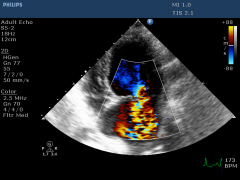

doppler-mitral-valve-disease-canine.jpg

mitral-valve-disease-dogs-canines.jpg